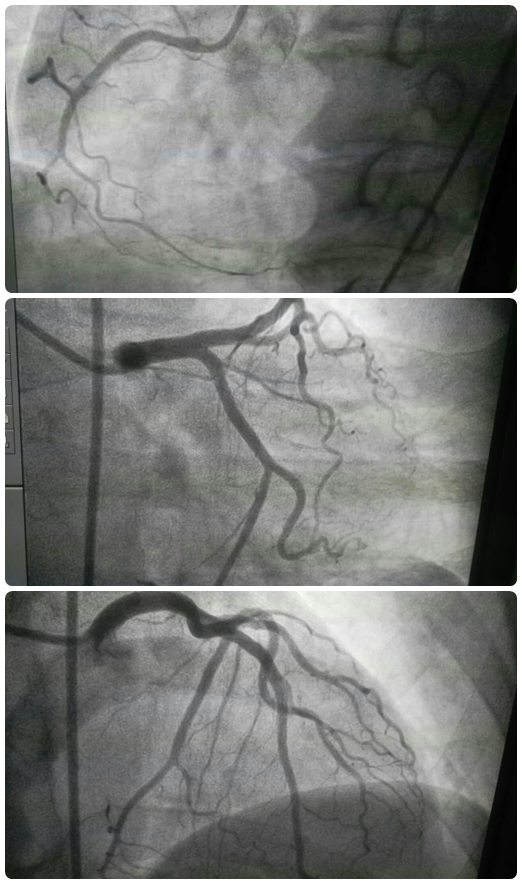

以往对于此类患者,在诊疗的过程中应在心内科做术前检查与准备及评估,择期至导管室行冠脉造影,然后再转至神经内科行术前准备及评估,再择日至导管室行脑血管造影,多次的麻醉、手术、造影为患者带来身体和经济上的双重负担。然而此次,为明确患者是否同时患有心脑血管疾病以及指导下一步治疗,心内三科经过与急诊科的商议,遵从“以患者为中心”的服务理念,决定采用“一站式”联合手术,我院心内三科与急诊科进行学科联合,成功救治了患者吴女士。此类联合手术不仅减少了病人多次麻醉的风险,同时也降低了近三分之一的医疗费用。据悉,这是我院首例采用联合手术治疗高危疑难心血管疾病的病例。

心内三科主治医生郑崔成介绍,外科手术和介入是治疗心脑血管疾病最为常见的两种手段,联合手术融合了外科及介入治疗的技术优势,在治疗冠心病、先天性心脏病、瓣膜心脏病等血管疾病时具有直观性、操作容易、方便定位、手术切口小、术后恢复快等优势。随着医学影像学设备和介入治疗器械的发展与成熟,联合手术成为治疗复杂疑难心血管疾病的发展方向。行此次联合手术的急诊科医生鄂永军也表示“一站式”联合手术可以一次性解决患者手术问题,无需在内科和外科间多次转移患者,从而避免多次麻醉和转运带来的风险。急诊科的工作忙碌、压力大,但鄂永军医生依旧挤出时间不断钻研专业知识,希望能在专业领域有进一步的提升,能为患者带来更高效优质的诊疗服务。